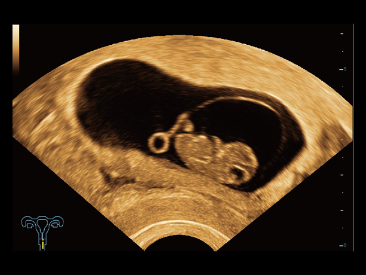

Desde que se fund├│ la compa?├Ła, Mindray ha explorado incansablemente nuevas formas de mejorar la confiabilidad del diagn├│stico. Con la revolucionaria tecnolog├Ła de ZONE Sonography?, la nueva plataforma ZST+ de Resona?7 lleva la calidad de la imagen por ecograf├Ła a un nivel superior mediante el procesamiento de datos de canal y la adquisici├│n de zona.

Adem├Īs de la calidad de imagen de primer nivel, Resona?7 tambi├®n mejora las capacidades de investigaci├│n cl├Łnica con el revolucionario V?Flow para la evaluaci├│n hemodin├Īmica vascular y con la adquisici├│n de planos m├Īs inteligente a partir de conjuntos de datos 3D para el diagn├│stico del SNC fetal. Al combinar el funcionamiento multit├Īctil basado en gestos m├Īs intuitivo y todas las caracter├Łsticas cl├Łnicas esenciales, Resona?7 realmente lidera las novedades en innovaci├│n de ecograf├Łas.